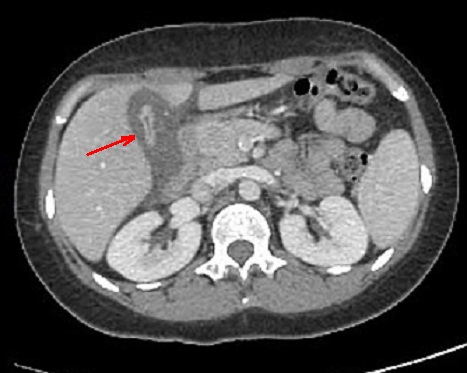

Aspect TDM de hepatite aigue

est image de hypoechogene dela parenchyme du foie ,

image de epaissisement de la paroi de la vesicule

biliaire . Coupe TDM axiale du foie |

|

Image de epaissisement de la

vesicule biliaire et image de adenopathie regionaire

periportal et hepato-duoenale . |